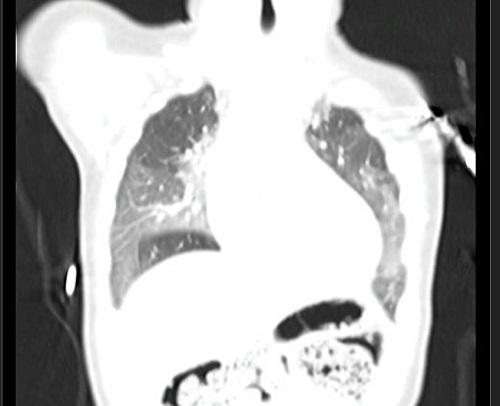

Se deriva a de nuevo a Neumología, donde se realiza TAC pulmonar, con el diagnóstico de HNE (Figuras 1 y 2).

Figura 1. TAC con hallazgos de HNE en ambos pulmones

Figura 1. TAC con hallazgos de HNE en ambos pulmones.

Las patologías intersticiales difusas pulmonares son un grupo de enfermedades raras que pueden inicialmente confundirse con otros cuadros respiratorios de mayor prevalencia, al ser su presentación inespecífica, siendo un reto para los pediatras.  Las células neuroendocrinas (derivadas del endodermo) se acumulan en el intersticio pulmonar de los lactantes con diagnóstico de HNE y secretan en el árbol bronquial histamina y el péptido liberador de gastrina, bombesina. La HNE suele acompañarse de hipoxemia crónica, retracciones intercostales, subcostales y subcrepitantes. No presenta tos ni estornudos. La radiografía de tórax puede ser normal o con signos de hiperinsuflación. El mejor método de imagen no invasivo es la TAC, cuyos hallazgos ─opacidades en vidrio esmerilado, en el lóbulo medio y la língula, así como los segmentos mediales del lóbulo superior e inferior─ son suficientes para realizar el diagnóstico. Se han descrito presentaciones atípicas de HNE, donde la TAC no es suficiente y se llega a una biopsia pulmonar. No existe un tratamiento específico y la pobre respuesta a los corticoides confirma el diagnóstico. El manejo consiste en dar soporte y cuidado preventivo: oxigenoterapia, soporte nutricional y tratamiento del reflujo gastroesofágico. No existen reportes de muertes, la evolución es crónica, pero con tendencia a la curación espontánea en meses o años.